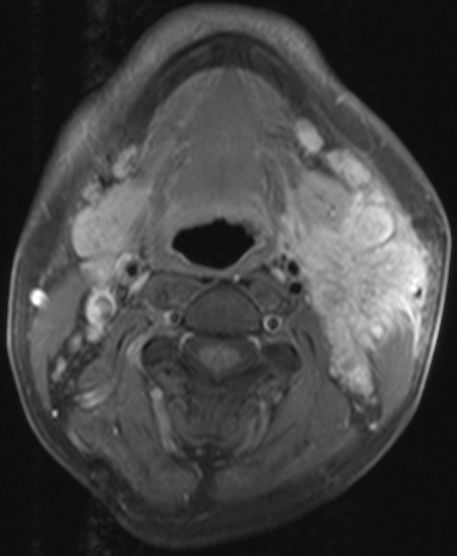

Hals-CUP 49jährige Frau mit Metastasen eines schleimbildenden Adenokarzinoms.